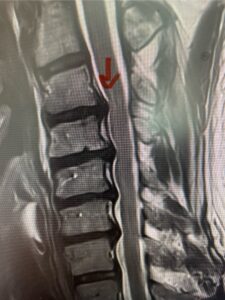

In this next case, this patient is a 47 year-old female who presents with intractable low back pain with severe pain, numbness, and weakness in the right lower extremity that had gotten progressively worse over a year. The patient had failed conservative management including physical therapy and epidurals. She was noted to have ⅘ weakness of plantar flexion. MRI demonstrated a large right L5-S1 disc herniation with severe compression of the descending right S1 nerve root (Fig 3). It was decided to perform a right L5-S1 hemilaminectomy for removal of the disc fragment and decompress the S1 nerve root. When you expose the disc, one must be certain to release any anterior adhesions to the nerve root in order to prevent a dural tear during retraction of the nerve root. It is also important to make sure during exposure and you finally encounter the dura after removing the ligamentum and fat, to make sure you are looking at the nerve root and not the main trunk of the thecal sac because if you don’t you can avulse or damage the nerve root if you retract the wrong structure.

Fig. 3a: Sagittal and axial T2-weighted lumbar MRI images demonstrating large right L5-S1 disc herniation (red arrows)

Fig. 3b